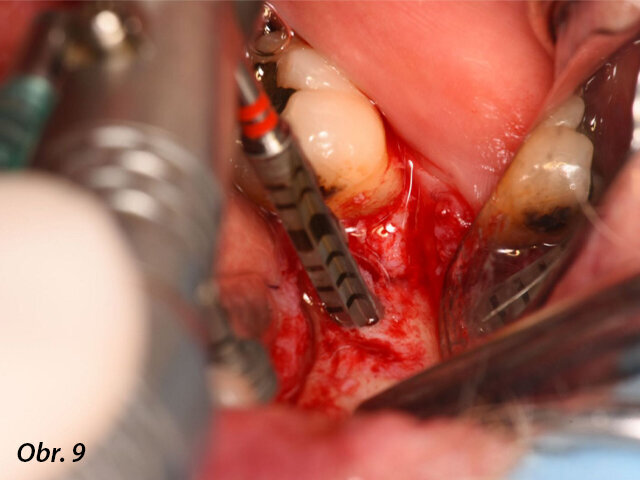

Meziodistálně byl implantát umístěn nejméně 1,5 mm od sousedního přirozeného zubu a mezi dvěma implantáty byla zachována vzdálenost 3,0 mm. Lůžka implantátů byla preparována podle pokynů výrobce a každý vrtáček byl použit za hojné irigace. Za účelem správné prostorové pozice implantátů byly použity paralelizační piny (obr. 8–10).